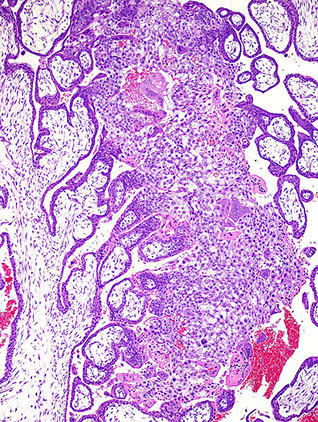

Figure 9. Villous stromal-vascular karyorrhexis ; Figure 10. Villous stromal-vascular karyorrhexis. Loss of integrity of the vascular wall; fragmentation and extravasation of red blood cells in the stroma with early septation [1]